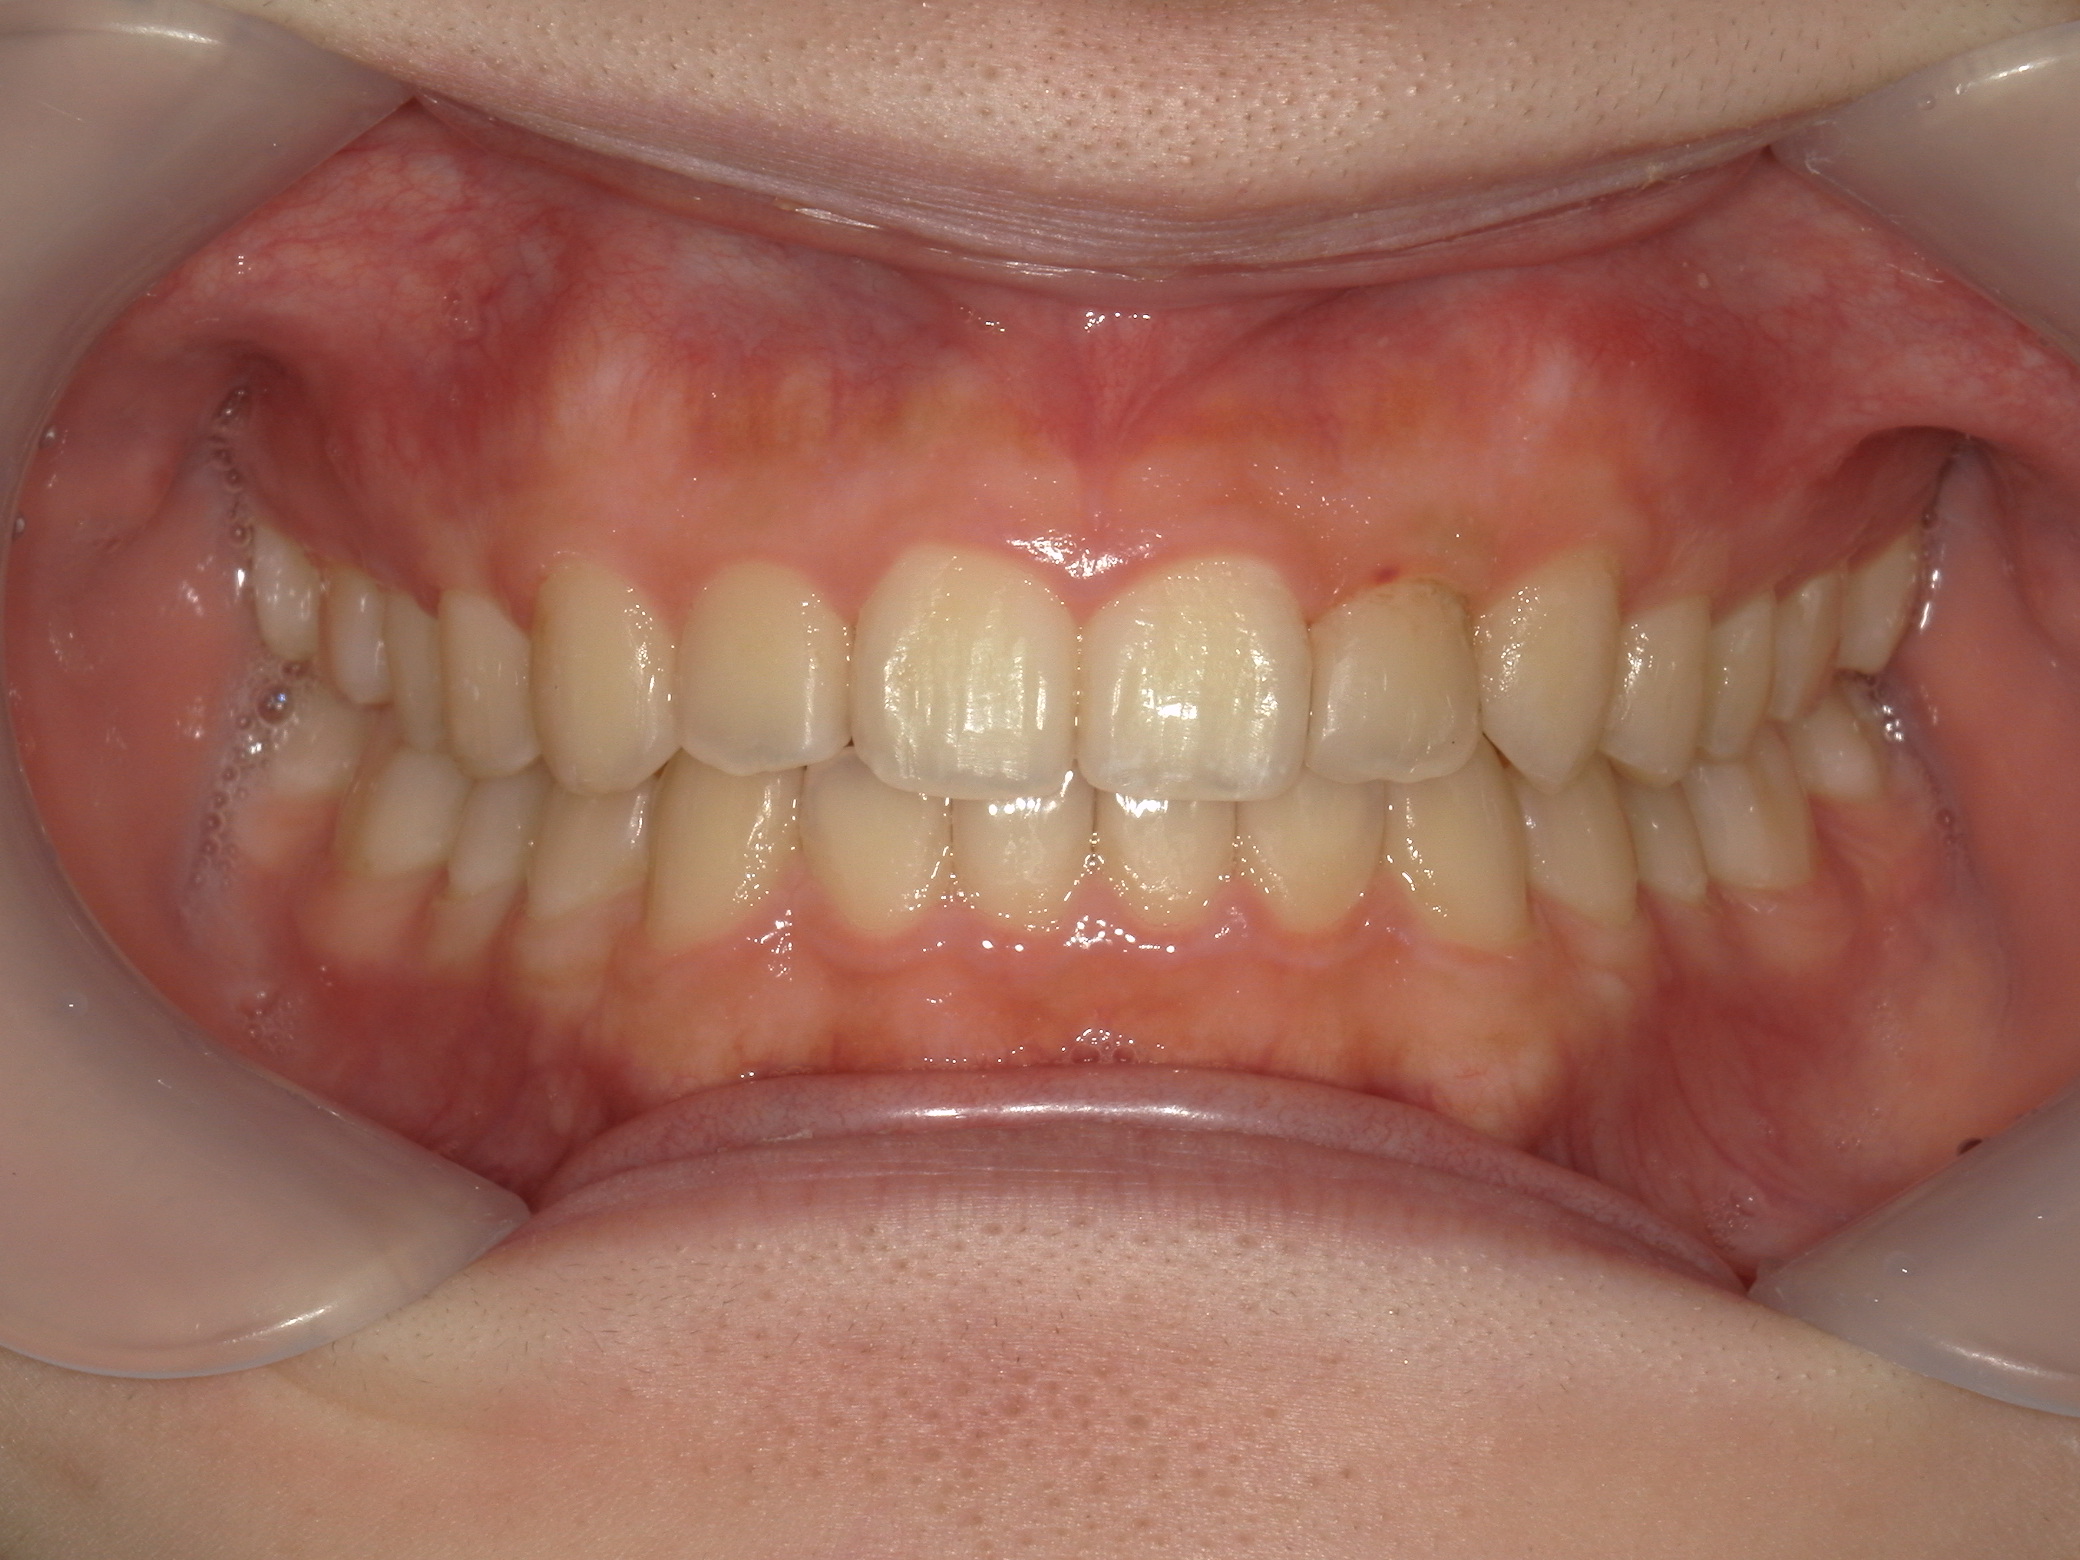

インビザライン矯正 症例(19)

主訴: 左上犬歯が出ているのが気になる

再設計3回

Ⅱ級ゴムを併用。